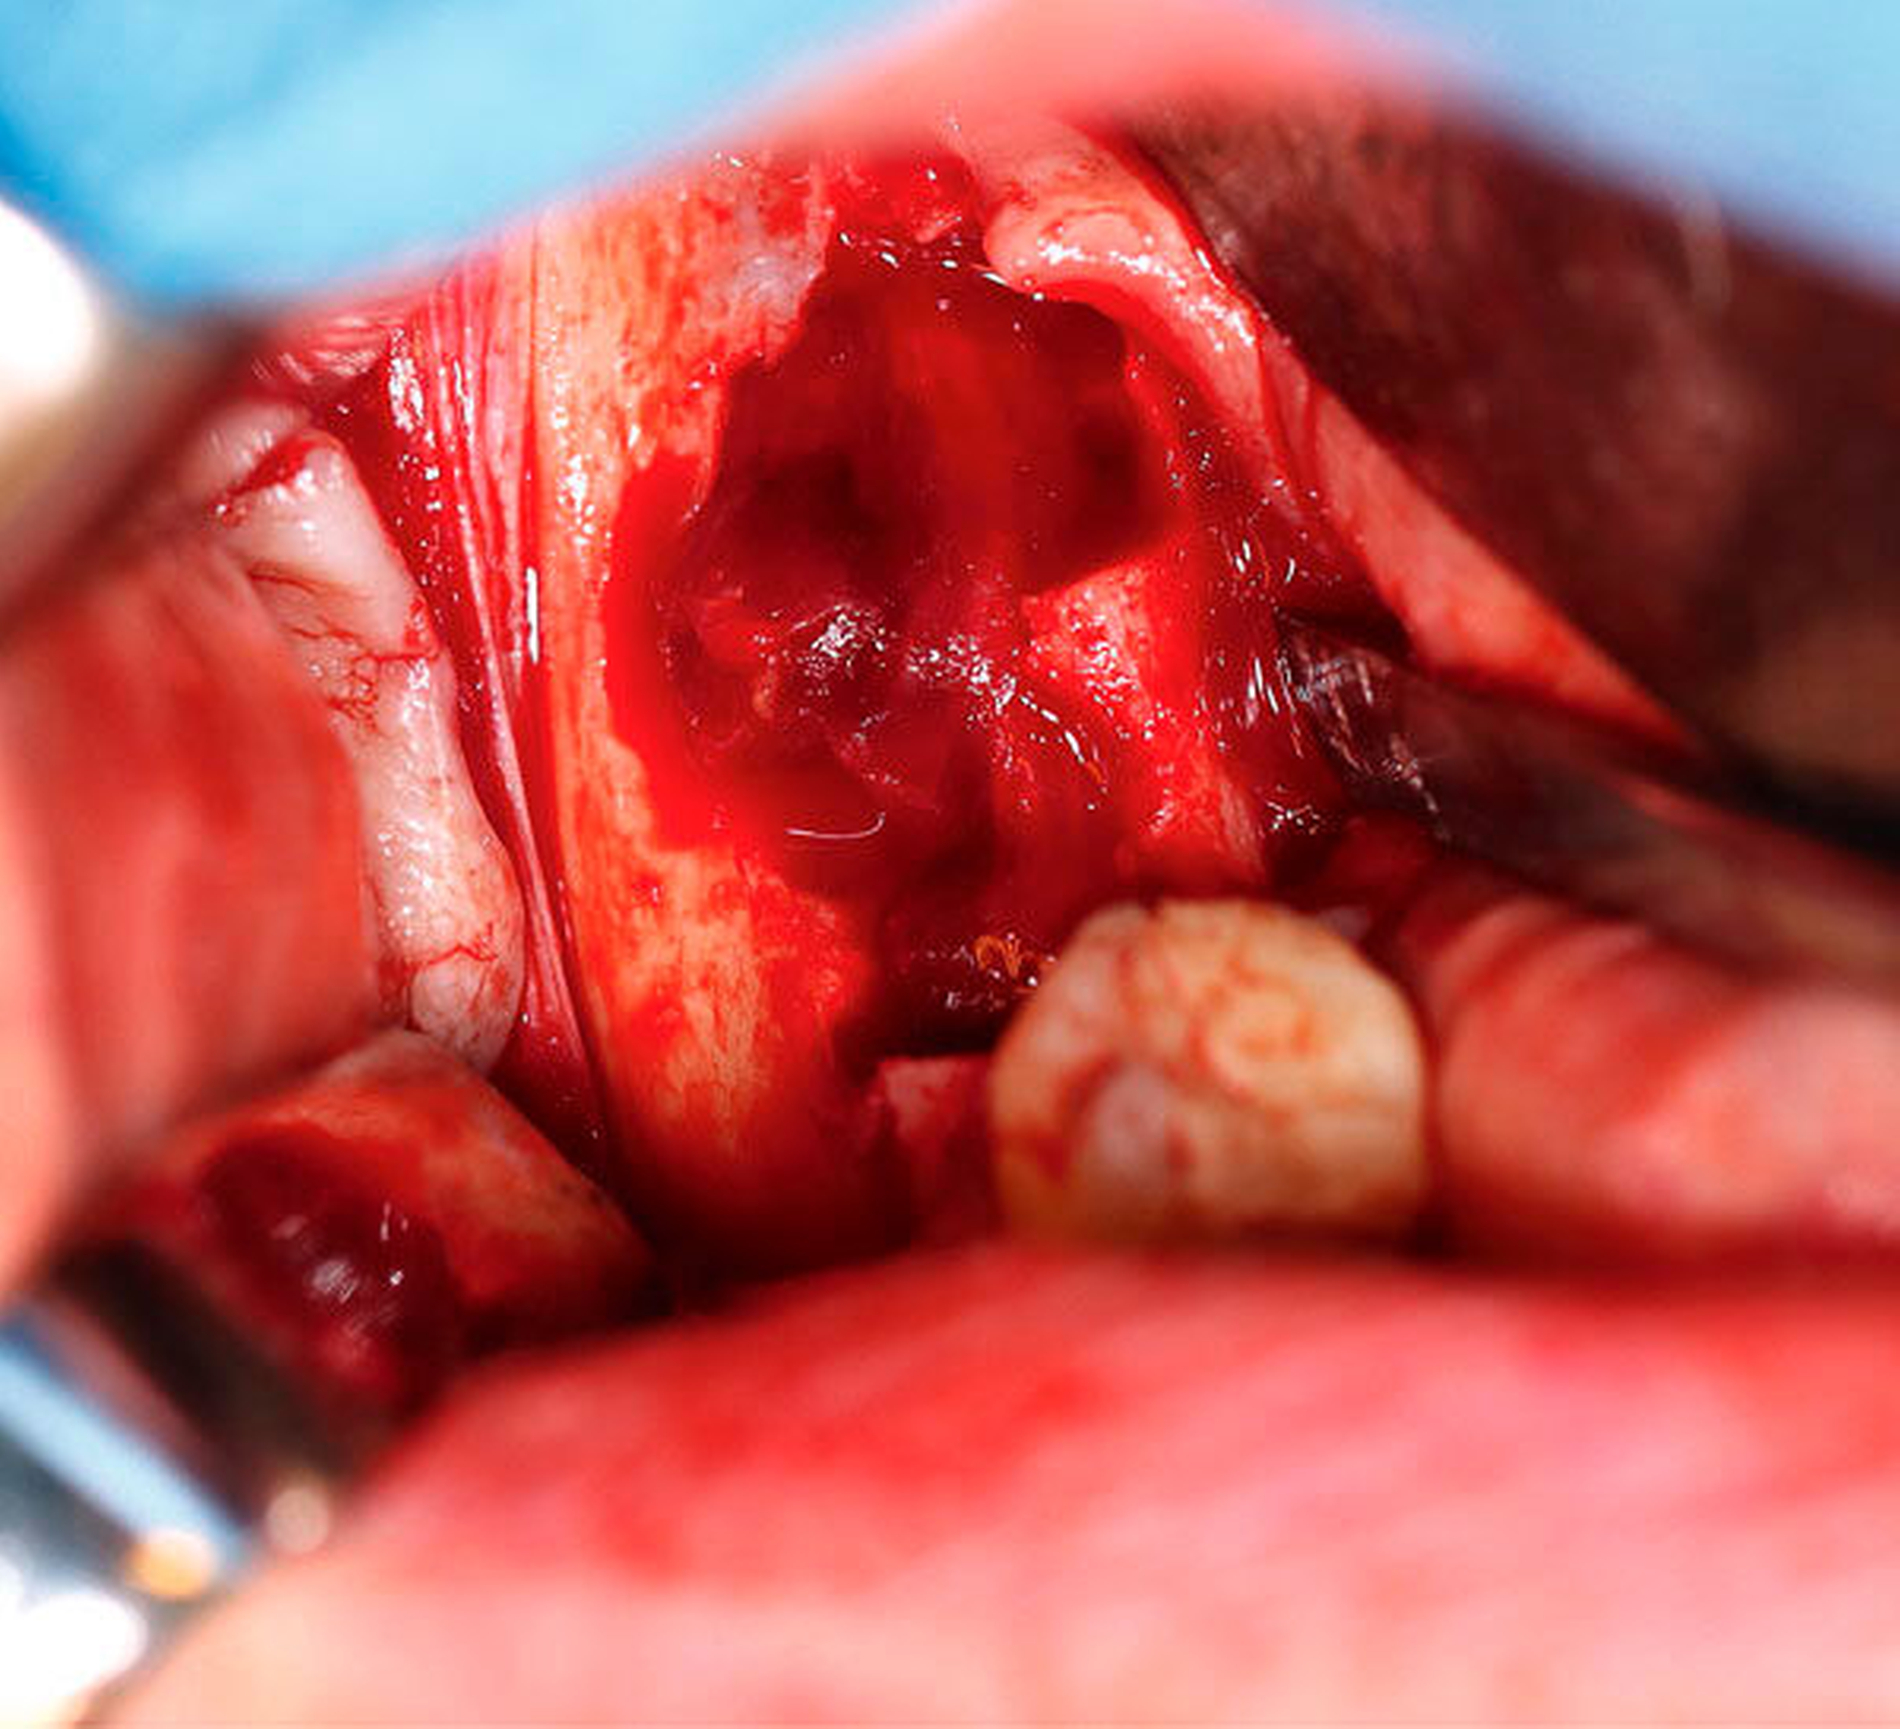

In Zusammenschau der klinischen und der radiologischen Befunde wurde die Verdachtsdiagnose eines Ameloblastoms beziehungsweise einer Keratozyste gestellt. Nach ausführlicher Beratung über mögliche Differenzialdiagnosen und Therapieoptionen entschied sich die Patientin zur Entfernung der Raumforderung in Intubationsnarkose. Hierbei erfolgte zunächst die Extraktion der teils stark gelockerten Zähne 47 und 48. In beiden Fällen konnte die vorher radiologisch auffällige Wurzelresorption ausgemacht werden (Abbildung 4). Nach der Extraktion breitete sich über die Extraktionsalveolen Zysteninhalt in die Mundhöhle aus (Abbildung 5). Im Anschluss wurde die Raumforderung unter Schonung des kaudal der Zyste verlaufenden Nervus alveolaris inferior exkaviert. Hierbei kam es im dorsalen Anteil der Kavität zu einer arteriellen Blutung, die nach elektrischer Kauterisation und Einbringen von Knochenwachs zum Stillstand gebracht werden konnte (Abbildung 6). Nach vorsichtiger modellierender Osteotomie folgten die Einlage eines Kollagenvlies und der mehrschichtige Wundverschluss.